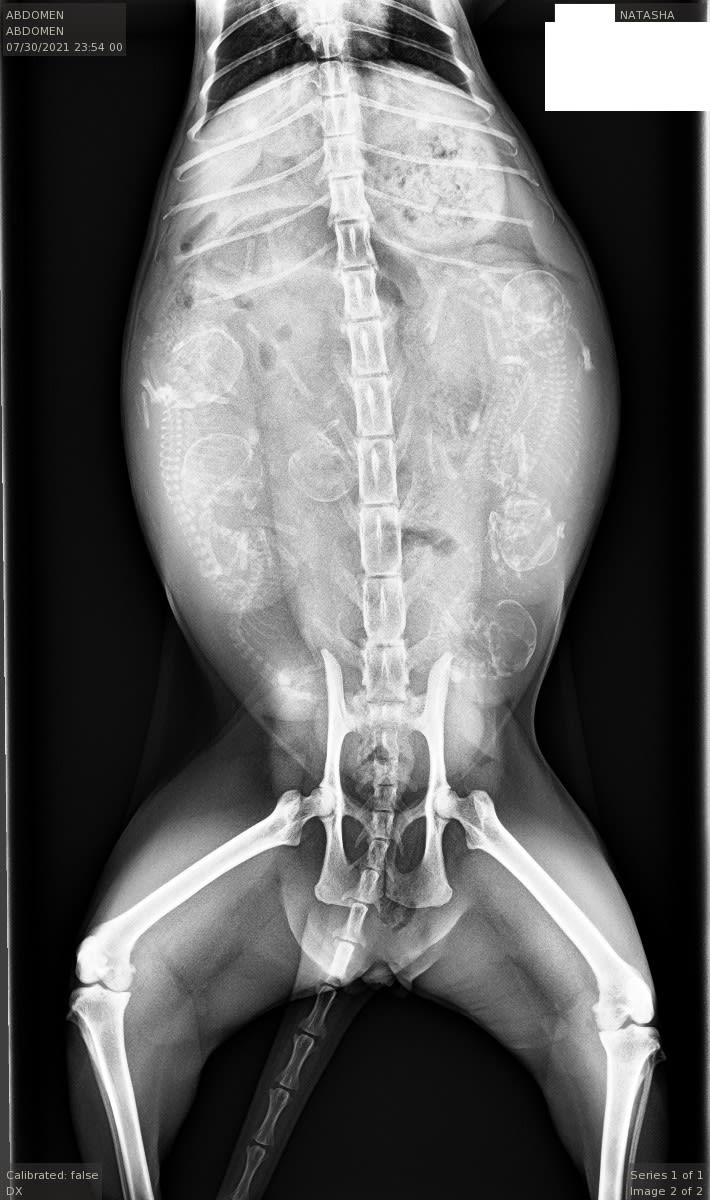

25Well, not yet. Vet says about a week and a half. Natasha (the kitty) is pretty small and I hope it all goes well. Vet also says she counts six. I’m not sure…some of my facebook friends say they count eight!

So exciting. I only count 6 little babies. Pretty cool I’ve never seen a pregnant cat X-ray before. You’ll have to update us and show us pics of the kittens. There’s something really special about kittens, their just so darn cute.

No arguing with that x-ray. That’s… Fascinating. I feel like aliens are coming

Fascinating. I count 12, is that OK?

In the 2nd pic, it looks like they are cuddled up in pairs. Would be cute to see if they continue to pair off like that after birth. Very cool pics – thanks for sharing!